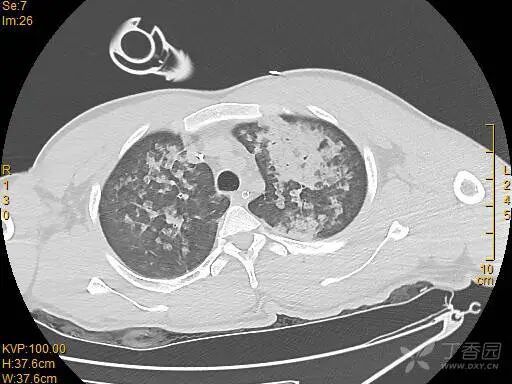

胸部 CT 如下: